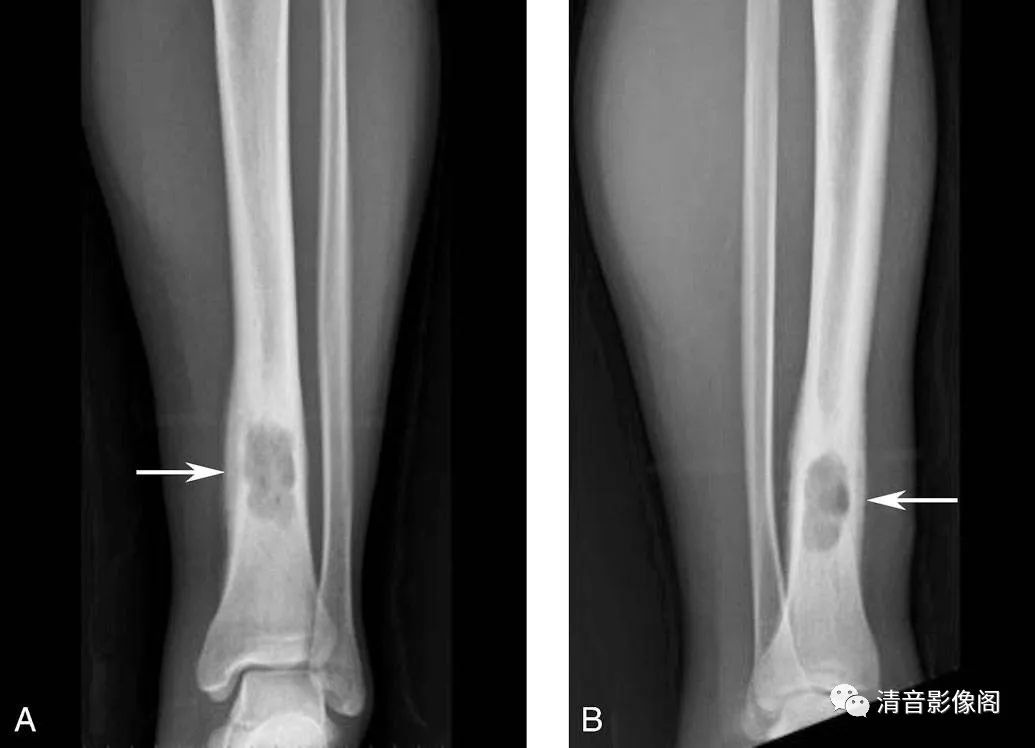

干骺端纤维性缺损

A. 踝关节X线正位;B. 踝关节X线侧位。

男,20岁。干骺端纤维性缺损,表现为皮质内的凹陷性缺损(箭头),周围伴硬化缘(箭),认为是由局部机械性拉力所造成的,若缺损不能修复进一步发展可演变为非骨化性纤维瘤,两者鉴别有一定的难度,一般认为后者硬化缘更宽,灶内有骨棘,呈皮质下膨胀而薄的葡萄串样透亮影。